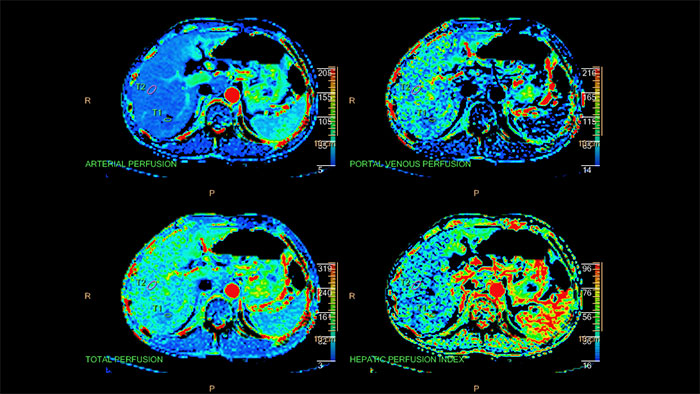

Quantifiable perfusion

CT Body Perfusion aids in the evaluation of acute or chronic stroke patients, as well as providing whole-organ or single-location liver perfusion.